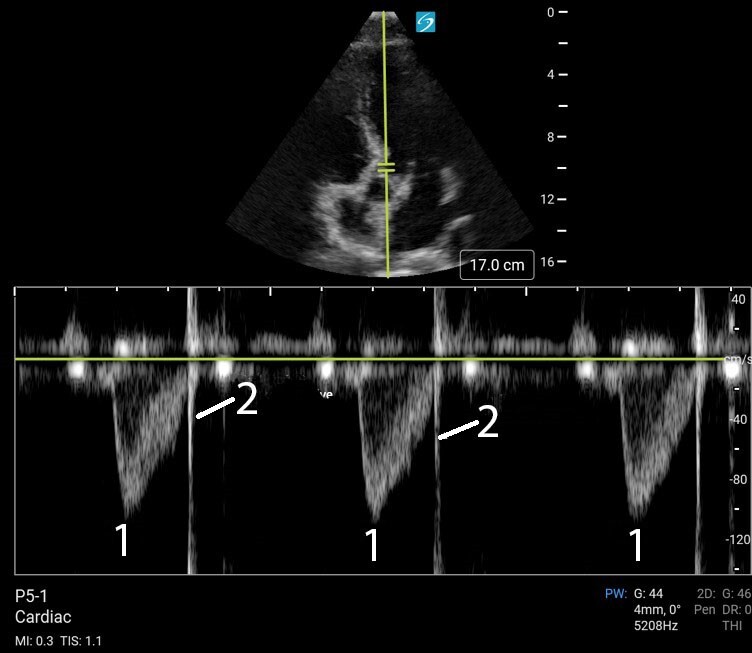

Cardiac 2 Determination of Stroke Volume VTI PW Doppler Image

1. Velocity Time Integral (VTI)

2. Closing Snap from Aortic Valve